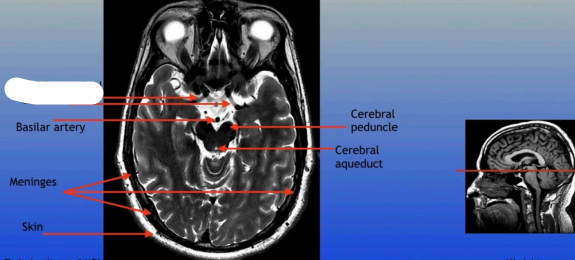

Basilar Artery

Meninges

Skin

Cerebral Peduncle

Cerebral Aqueduct